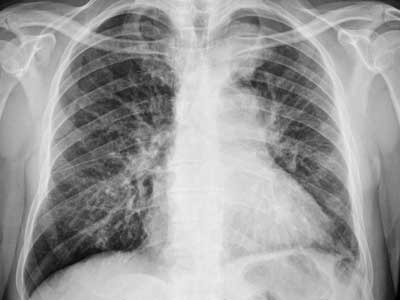

X-rays can provide valuable information early in the process of diagnosing a patient. A CT scan permits the physician to determine the size, location and shape of any mass or tumor. CT scans can also distinguish between fluid and solid tissue.